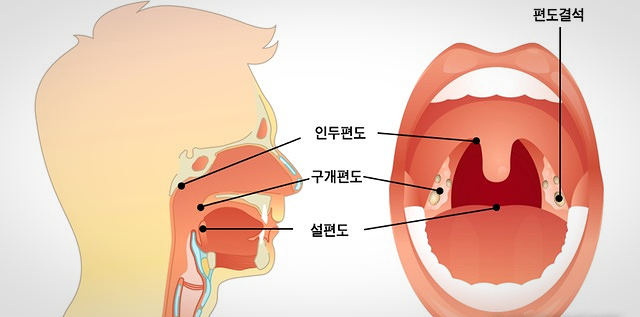

안녕하세요^ 무사하고 건강에 행복한 삶을 영위하고 싶은 생활건강 인플루언서 땡큐입니다.^^ 편도선에 생기는 악취를 가진 좁은 정도의 크기부터 손톱 정도의 크기까지 다양합니다.입 냄새를 유발하는 원인으로 구개편도선 표면에 존재하는 편도선이라는 부위에서 분비된 침소체가 구강 내 이물질과 섞여 생깁니다. 편도결석은 칼슘의 인산염과 탄산염으로 구성되어 있어 침 분비나 혀의 움직임에 의해 삼키거나 기침에 의해 반사적으로 외부로 나오게 됩니다. 편도결석은 보통 나쁜 냄새를 가지고 있어 휘발성 황화합물을 비롯한 악취를 유발하는 원인물질이 되고 식욕까지 변하기도 합니다. 심한 경우 병원에서 편도 구멍을 봉합하는 수술을 받아야 합니다. 그럼 편도결석의 원인과 증상, 편도결석을 빼는 방법에 대해 자세히 살펴보겠습니다.

편도결석의 원인

편도선이 표면의 편도선이나 내부에 세균, 백혈구, 세균의 시체, 지방산, 음식물 잔류물 등이 쌓여 생깁니다. 자연적으로 배설되는 경우가 많은데 배설되는 편도선 표면의 출구나 소와 부분이 좁은 경우 편도선 내부 속에 굳어져 큰 몸이 될 수 있습니다.